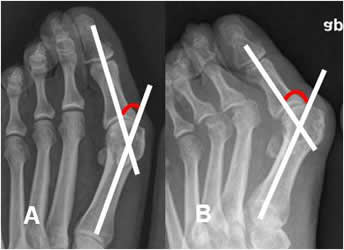

Medido en Rx AP. Se traza entre los ejes longitudinales del 1º metatarsiano y la falange proximal del hallux. (1). El ángulo normal debe ser inferior a 15º. Valores superiores se considera hallux valgus. (2). (Fig 92 y 93).

Fig 92. Angulo de hallux valgus.

Rx AP. Angulo de hallux valgus normal.

Fig 93. Hallux valgus.

A y B: Rx AP. Incremento de los ángulos, por hallux valgus.